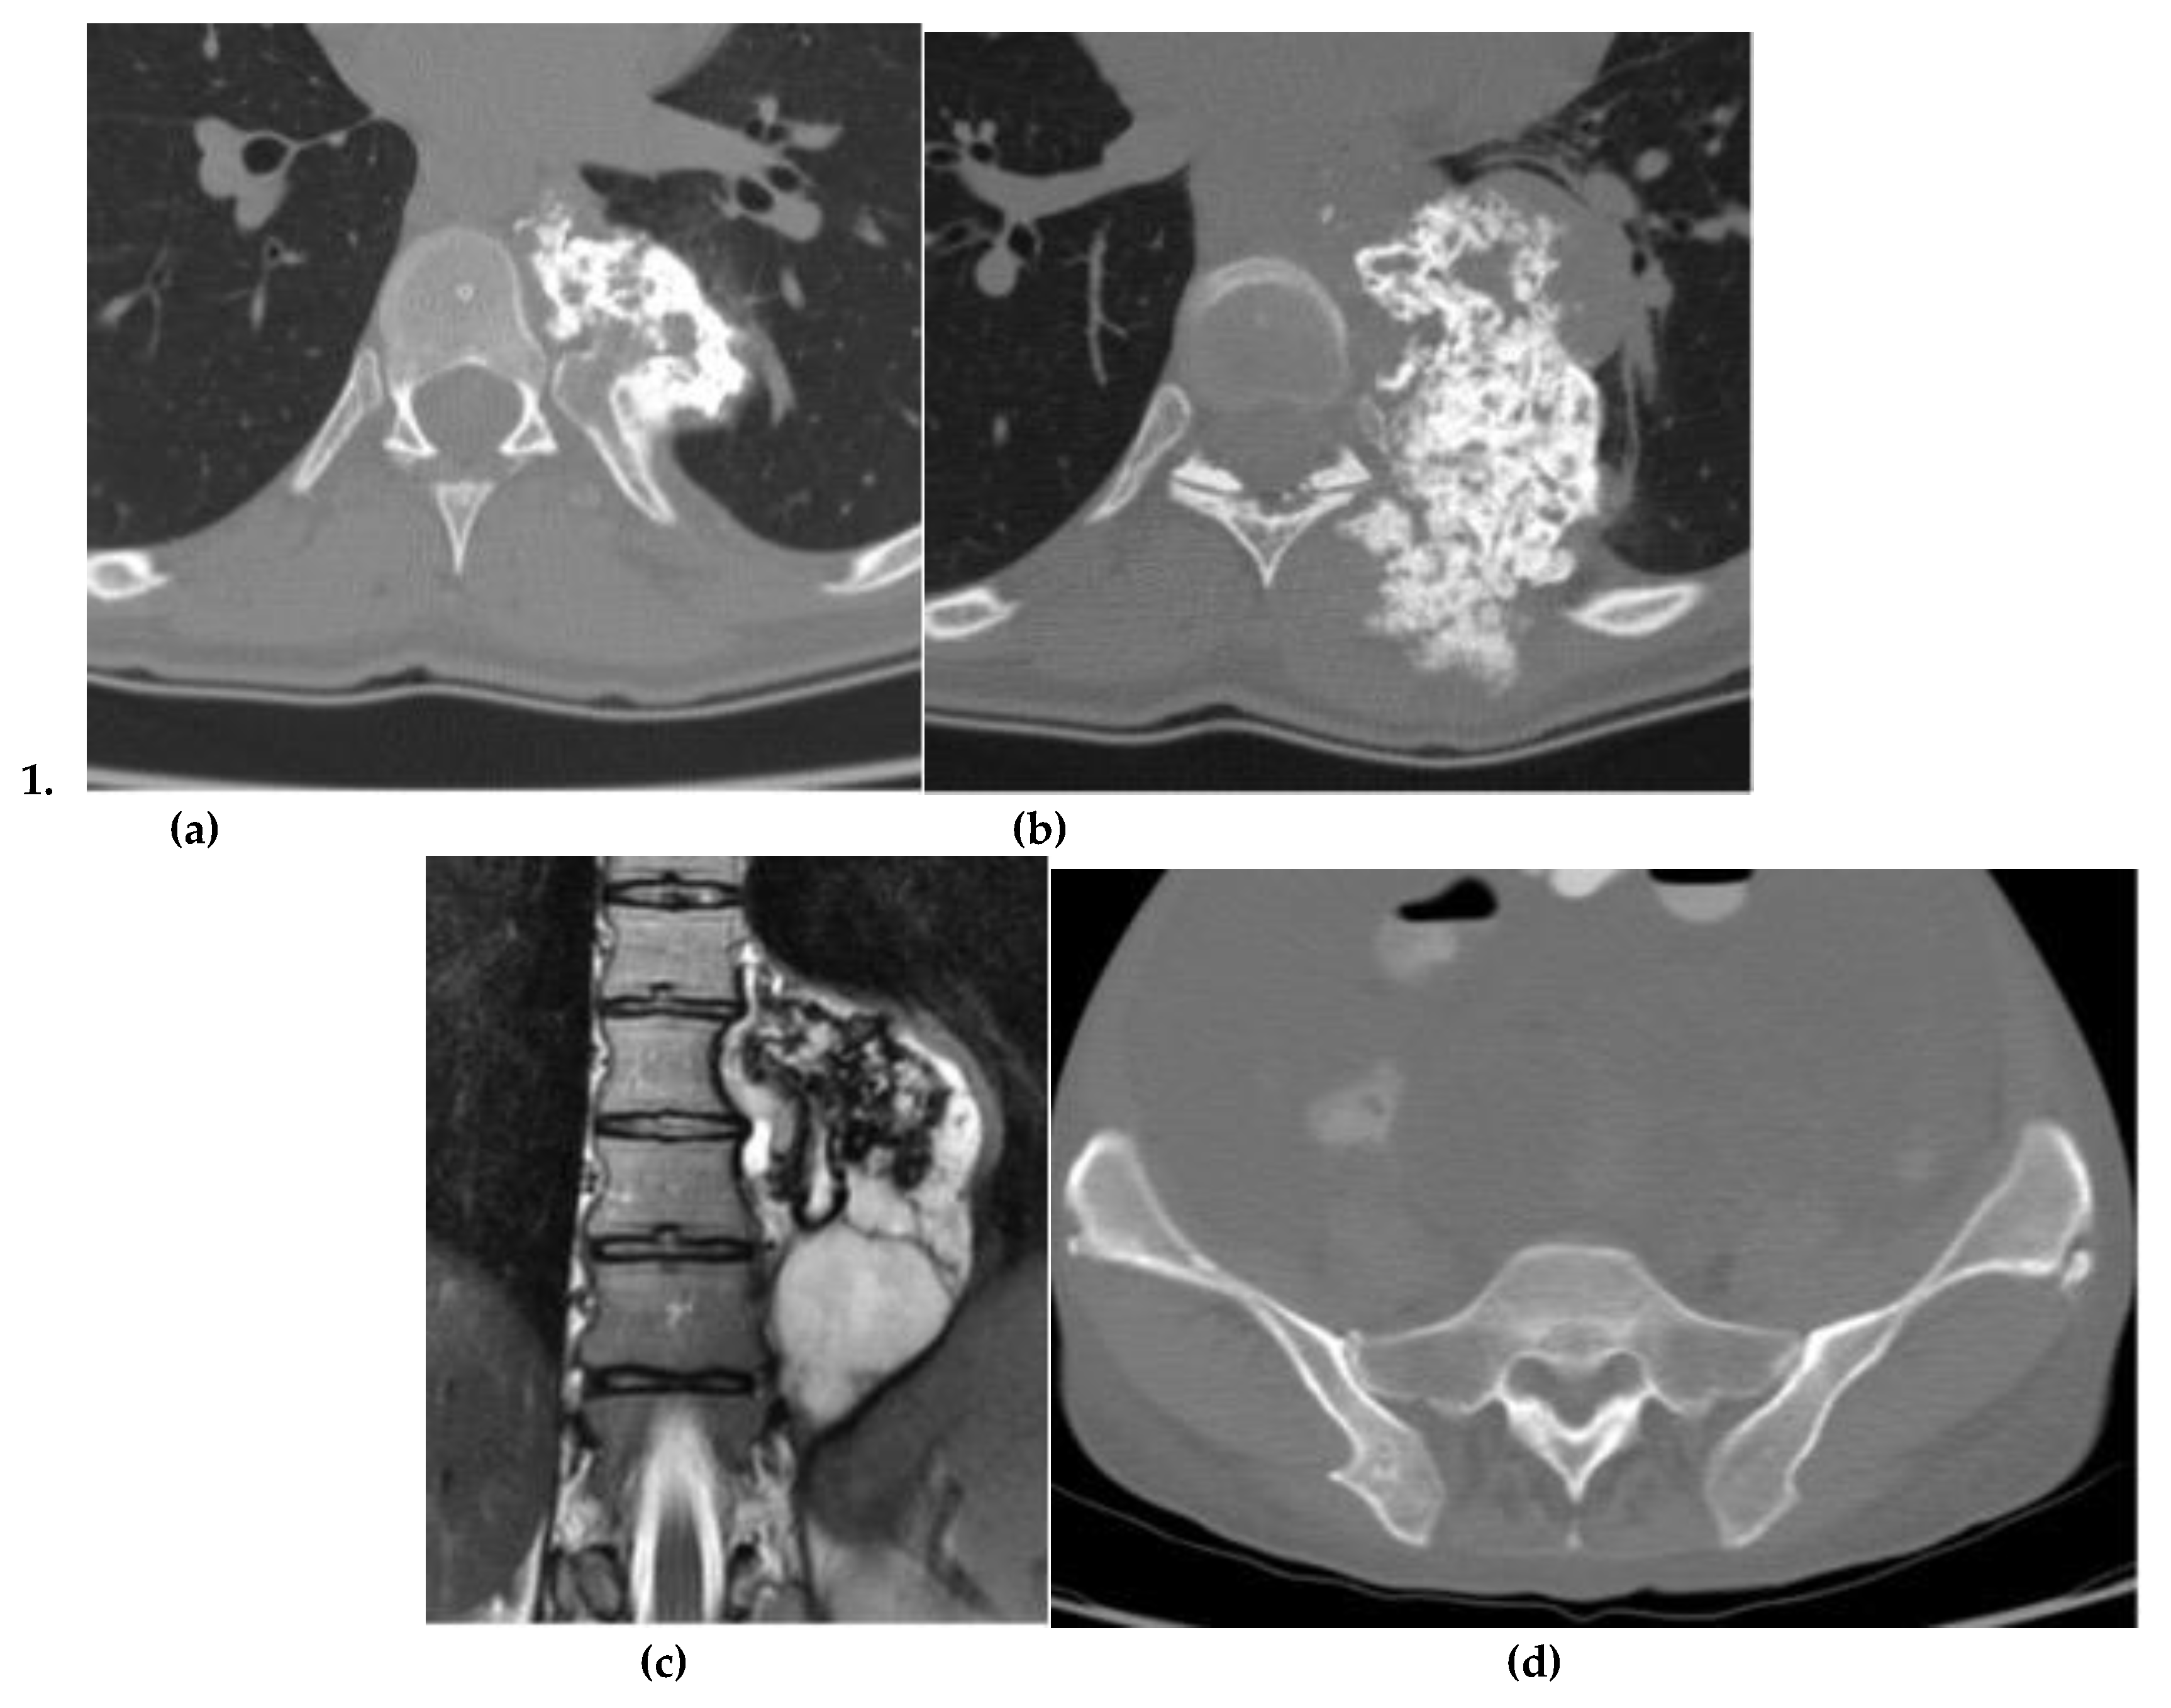

Osteosarcoma

Chondrosarcoma

Chordoma